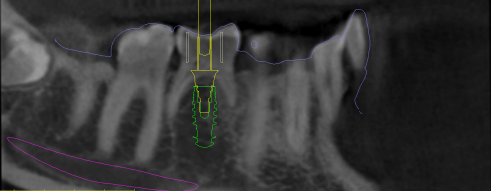

Diagnóstico y planificación digital prequirúrgica

Nuestro equipo de Implantología diagnosticará y valorará mediante imágenes 3D (tomografías) y modelos digitales; si se es candidato para la colocación de un implante dental. Si la respuesta es sí* se planificará digitalmente su posición y diseño protésico; para minimizar el margen de error en la cirugía y crear un plan de tratamiento perfecto para cada paciente.